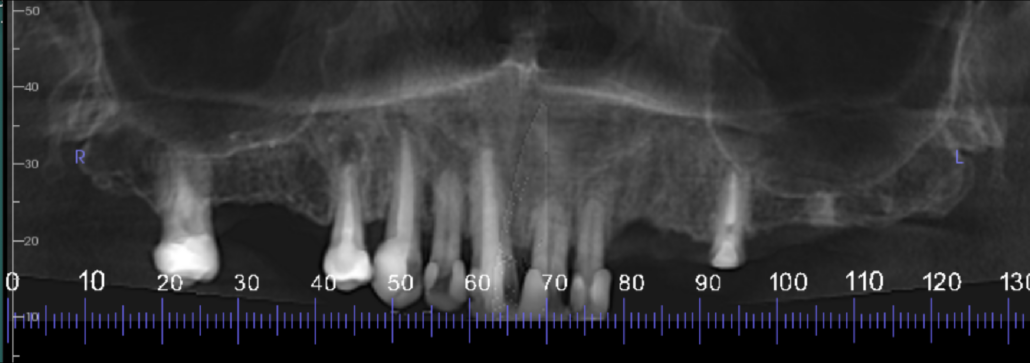

Reconstructed panoramic view of the maxilla

UR7-4 region cross sections at 2 mm intervals. Moderate loss in vertical bone height. The UR4 is root treated. The buccal root filling is short of the apex with 3-4 mm wide apical radiolucency. The palatal root canal is filled to the apex with 0.5-1 mm wide radiolucency

UL3-4 region cross sections at 3 mm intervals. Mild loss in vertical bone height. Moderate density cortical and trabeculae bone

UL5-7 region cross sections at 3 mm intervals. Moderate loss in vertical bone height. Moderate density cortical and trabeculae bone